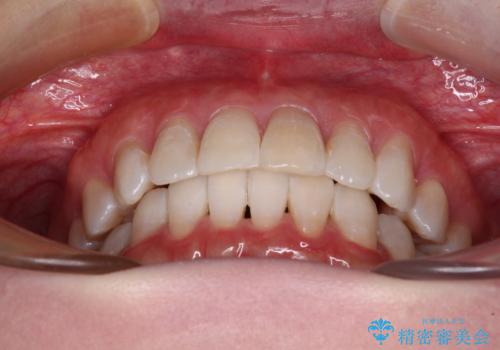

前歯の突出感とデコボコをインビザライン矯正で改善

- 上下前歯の突出感とデコボコを気にして来院された患者様です。

インビザラインによる上下歯列の側方拡大と後方移動、IPR(歯と歯の間を削る)にるスペースの獲得により歯列を整えることとしました。

骨格的な左右差があったため、上下の正中を合わせることができませんでした。

骨格の差は改善できないため、奥歯の咬み合わせに物足りなさを感じましたが、奥歯の咬み合わせによる不自由はなく、口元の突出感も改善することができました。